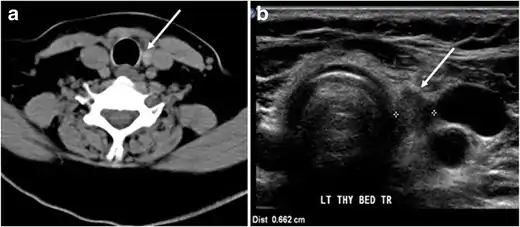

Fig. 7. A 51-year-old female patient post total thyroidectomy for PTC with elevated thyroglobulin measurement. an Axial non-enhanced CT scan of the neck at the level of the thyroid bed demonstrates a well-defined, rounded, homogenously dense soft tissue situated between the trachea and left internal jugular vein (white arrow). b Transverse ultrasound image of the neck demonstrates a well-defined, homogeneous, hypoechoic soft tissue nodule measuring 6 mm (white arrow) with no detected micro-calcifications. Biopsy showed a predominantly residual normal thyroid tissue with micro-foci of PTC.[1]

Fig. 8. A 48-year-old male patient post total thyroidectomy with PTC recurrence. a Transverse greyscale ultrasound of the neck demonstrates a left thyroid bed heterogeneous, predominantly hypoechoic irregular lesion with calcifications (white arrow). b A spot image of iodine 123 total body scan of the neck demonstrate a focus of abnormal radiotracer uptake at the left thyroid bed (Black arrows) between the annotated markers. c Enhanced axial CT scan of the neck demonstrates an enhancing large left thyroid bed mass (white arrow) with no calcifications. The lesion exerts a mass effect on the oesophagus (black arrow) and is inseparable from the trachea.[1]